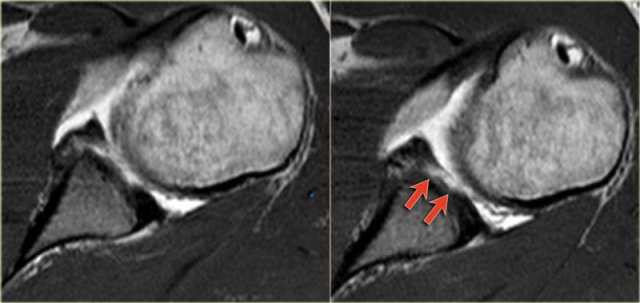

On MR a Hill-Sachs defect is seen at or above the level of the coracoid process.

Hill-Sachs is a posterolateral depression of the humeral head.

It is above or at the level of the coracoid in the first 18 mm of the proximal humeral head.

It is seen in 75-100% of patients with anterior instability.

The physiologic groove in the humerus or cysts and erosions at the attachment site of the infraspinatus tendon can simulate a Hill-Sachs, but usually this is not a diagnostic problem (figure).

First notice the Hill-Sachs defect indicating a prior anterior dislocation (blue arrow).